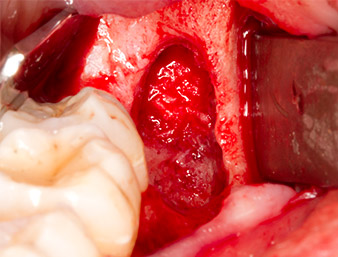

Tras una anestesia local y por conducción, el campo quirúrgico se abrió mediante los tejidos blandos para tener un acceso bucal-retromolar y se dejó expuesto (figura 3).

El tejido situado por encima del resto radicular no se había osificado por completo y constaba en su mayor parte de un tejido granulado con alteraciones inflamatorias (figura 4).